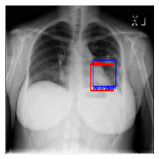

CXR8 [21] is one of the most commonly accessible radio-logical examination for many lung diseases. The data consists of 112,120 images collected by 30,805 patients. As shown in Table I, nine class labels of normal state and eight diseases including cancer are defined for classification. The data is divided into training set and test set, and the classification accuracy and ROC curve with several well-known deep network such as VGG16, GoogLeNet, and ResNet, are reported on the original paper [21]. In addition, 984 Bounding Boxes (B-Box) are provided for localization. Fig. 5 shows image examples of CXR8. The red rectangle in the image shows given B-Box.

Refer to caption

(a) Atelectasis

(b) Mass

Figure 5: Image examples of CXR8